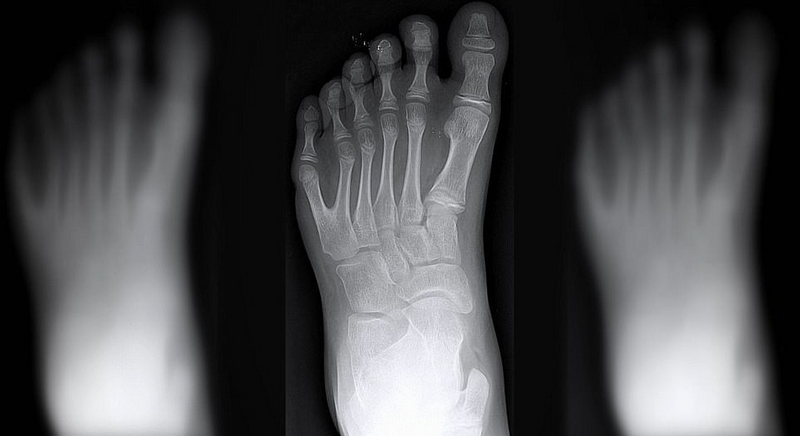

畸形对于大多数家庭而言都是噩耗。然而达席尔瓦家族却将其家族遗传的六指视若珍宝。23位家庭成员中共有14位患有多指畸形,他们的手指和脚趾都比常人多出2根。

一般来说,大部分多指畸形的患者无法使用他们多出来的手指,可是达席尔瓦家族的多指却可以正常使用。于是这种畸形非但没有成为阻碍,反而被认为是上天赐予的财富,他们可以利用多指的优势在音乐和足球等方面独占鳌头。譬如新生儿的哥哥乔阿西斯(Joao Assis),他是一名守门员。他说,六指可以让他在抓球时有更多着力点,所以球很难从他手里逃脱。